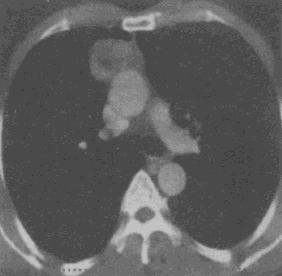

男,45岁,眼睑上抬困难3个月,CT检查如图。最可能的CT诊断为 YZ332_1_47_21.gif

• A.畸胎瘤

• B.神经纤维瘤

• C.胸腺瘤

• D.淋巴结增生

• E.纵隔型肺癌